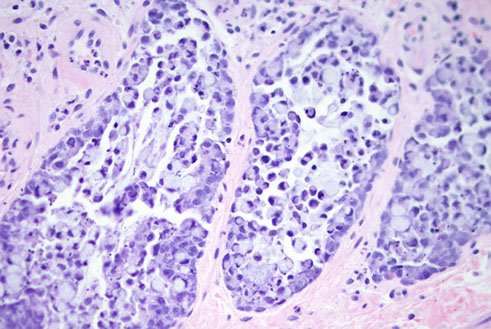

Pyloric gland adenoma

Pyloric gland adenoma (PGA)

Neoplastic polyp ; not very common, F>M; assoc c AMAG, may have H pylori

- can be found in stomach(esp in the body), g-bladda, duodenum, main panc duct

- may be assoc c dysplasia in FAP pts

Micro: closely packed pyloric type glands c cuboidal to low columnar epithelium c pale to reddish ground glass cytoplasm

- nuclei round w/o nucleoli

- commonly have foci of dysplasia (HG>LG) / ca

IHC: (+) MUC6 (pyloric gland mucin), MUC5AC (foveolar mucin)

- neg MUC2 (intestinal mucin), CDX2

- areas of transition from gastric to intestinal diff can show (+) MUC2 and CD10

Tx: complete excision